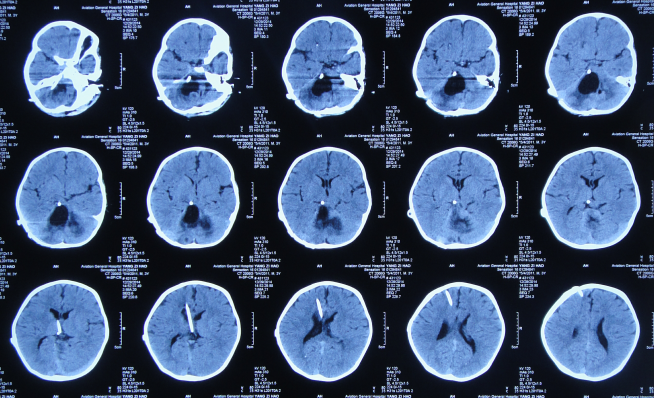

颅脑ct怎么看?正常和异常影像分别是什么?_脑室

10张图搞定正常头颅ct断层解剖